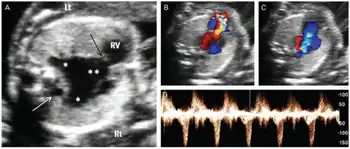

| Prenatal ultrasonographic findings of absent pulmonary valve syndrome a) Marked dilatation of main and branch pulmonary arteries b-d) color and pulsed wave Doppler ultrasound shows to-and-fro pattern of pulmonary stenosis and regurgitation | |